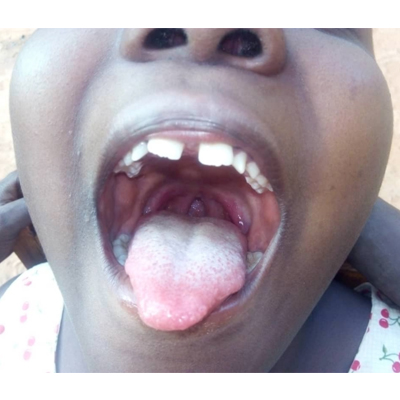

Oral Health Solutions Organization (OHSO), founded in October 2019, is an active non-governmental organisation (NGO) at the forefront of improving oral health in Rwanda, through oral health promotion, oral disease prevention and advocacy. The NGO vies to complement adequately Government effort to promote health and prevent diseases through school and maternal health settings. We adopt proactive engagement across all platforms in working alongside various government ministries, institutions,NGOs,dental professionals and the public.